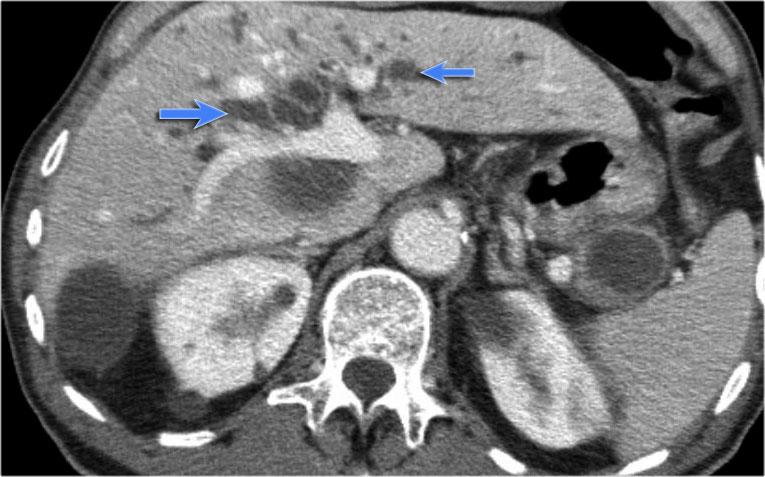

Ở đuôi tụy có tổn thương dạng nang với sẹo trung tâm kèm vôi hóa (mũi tên).

Mặc dù một số nang có kích thước lớn hơn 2 cm, hình ảnh này vẫn điển hình cho u nang tuyến thanh dịch, do có sẹo trung tâm, hình ảnh đa thùy và bờ viền thùy múi.

Bệnh nhân này có các triệu chứng đau bụng được quy cho khối u, khối u đã được phẫu thuật cắt bỏ và kết quả giải phẫu bệnh xác nhận là u nang tuyến thanh dịch.

Đây là bệnh phẩm sau phẫu thuật cắt bỏ.

Khối u dính vào lách, do đó lách cũng phải được cắt bỏ cùng.